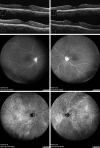

Nivolumab is an anti-programmed cell death protein 1 monoclonal antibody that is used to treat metastatic cutaneous malignant melanoma. Although bilateral uveitis has been reported as a side effect of nivolumab administration, there are few reports of Vogt-Koyanagi-Harada disease (VKH)-like uveitis. We report such a case. A 63-year-old woman with metastatic cutaneous malignant melanoma experienced visual loss in both eyes 10 days after her second nivolumab injection. Her decimal best-corrected visual acuity (BCVA) was 0.7 in the right eye and 0.4 in the left eye. Examination revealed bilateral granulomatous keratic precipitates and posterior synechiae in the left eye. Optical coherence tomography showed multiple sites of serous retinal detachment (SRD) in the left eye and wavy retinal pigment epithelium in both eyes. Fluorescein angiography revealed multiple pinpoint-sized areas of leakage in both eyes and active leakage from the disc in her right eye. Indocyanine green angiography (IA) showed choroidal hyperfluorescence due to choroidal vascular leakage, with hypofluorescent dark spots during the late phase. These findings supported a diagnosis of VKH-like uveitis following nivolumab injections. Nivolumab was discontinued because of headache. Anterior chamber inflammation disappeared 3 weeks after starting topical corticosteroid treatment, and the SRD disappeared within 3 months. Her decimal BCVA recovered to 1.0 in the right eye and to 0.9 in the left eye. Also, the fluorescein angiography and IA findings had improved by 4 months. We concluded that careful follow-up is required after nivolumab treatment because VKH-like panuveitis might develop.